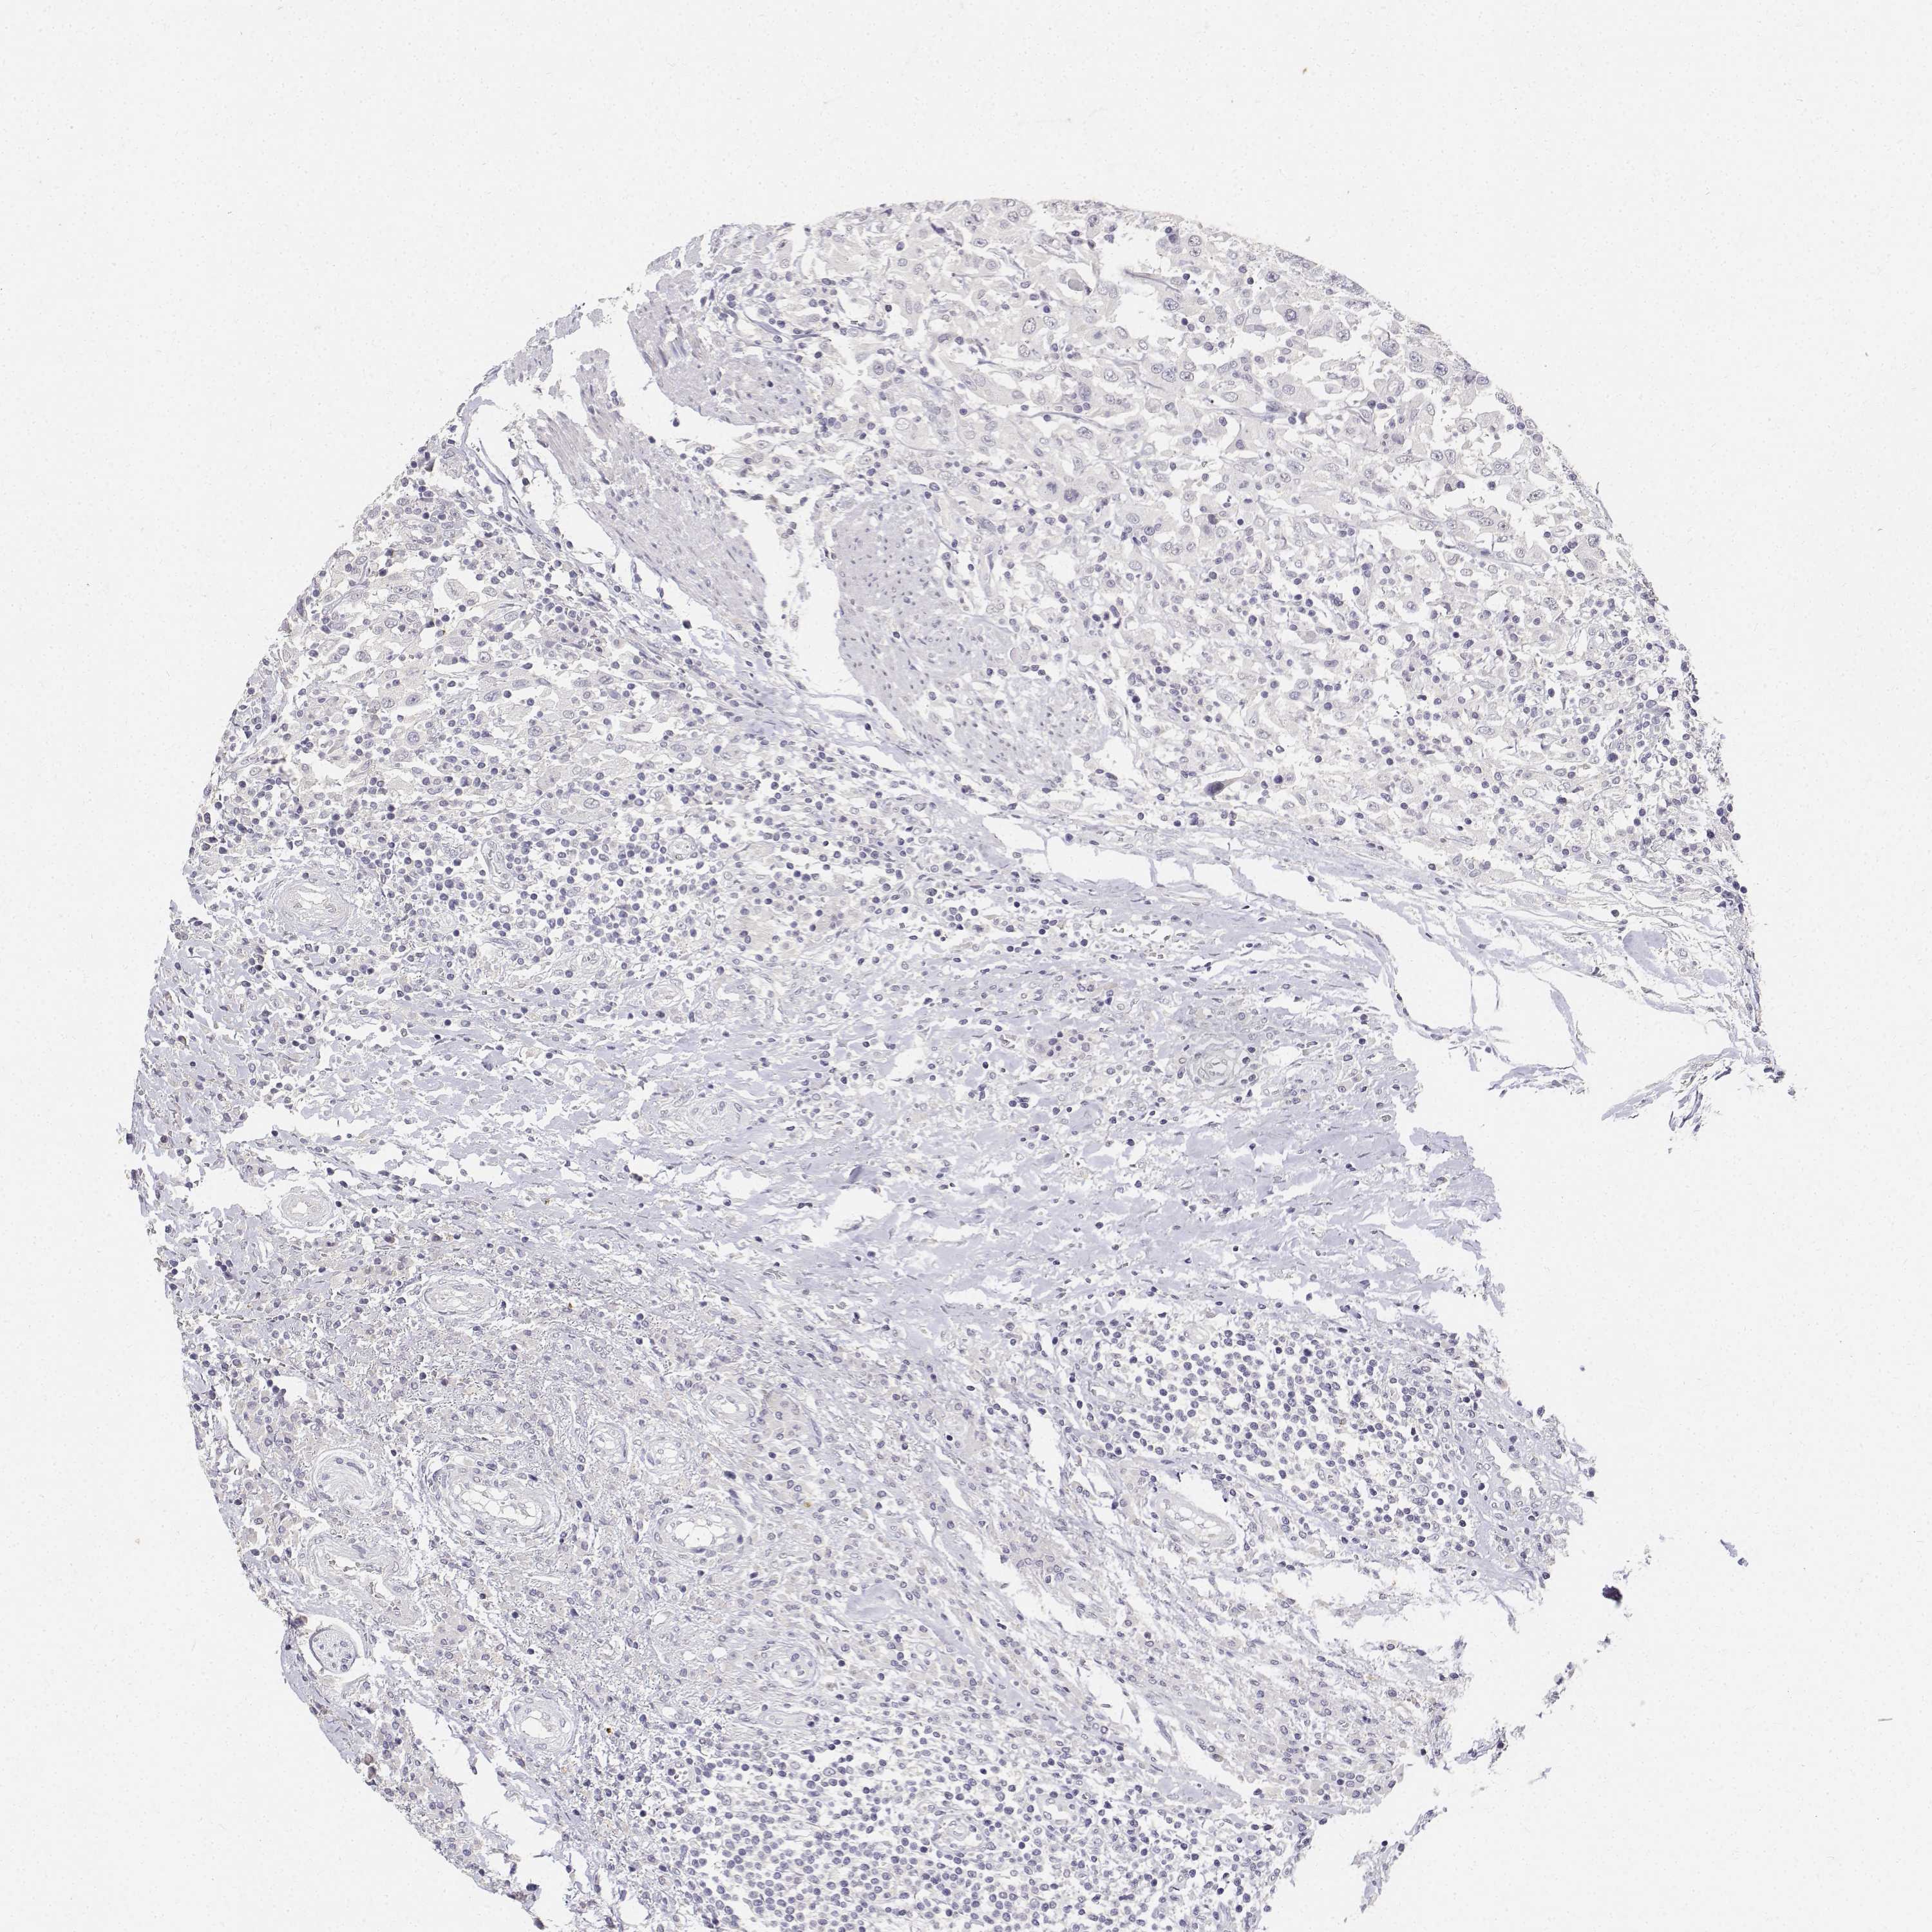

UROTHELIAL CANCER - Protein expressioni

A mouse-over function shows sample information and annotation data. Click on an image to view it in a full screen mode. Samples can be filtered based on level of antibody staining by selecting one or several of the following categories: high, medium, low and not detected. The assay and annotation is described here.

Note that samples used for immunohistochemistry by the Human Protein Atlas do not correspond to samples in the TCGA dataset.

Antibody stainingi

Antibody staining in the annotated cell types in the current human tissue is reported as not detected, low, medium, or high, based on conventional immunohistochemistry profiling in selected tissues. This score is based on the combination of the staining intensity and fraction of stained cells.

Each image is clickable and will lead to virtual microscopy that enables deeper exploration of all samples and also displays staining intensity scores, fraction scores and subcellular localization as well as patient and tissue information for each sample.

Antibody HPA020108

Antibody HPA029473

Antibody CAB016762

Staining

High

Medium

Low

Not detected

Intensity

Strong

Moderate

Weak

Negative

Quantity

>75%

75%-25%

<25%

None

Location

Nuclear

Cytoplasmic/membranous

Cytoplasmic/membranous,nuclear

Urothelial carcinoma, High grade

Urothelial carcinoma, NOS

Urothelial carcinoma, Low grade